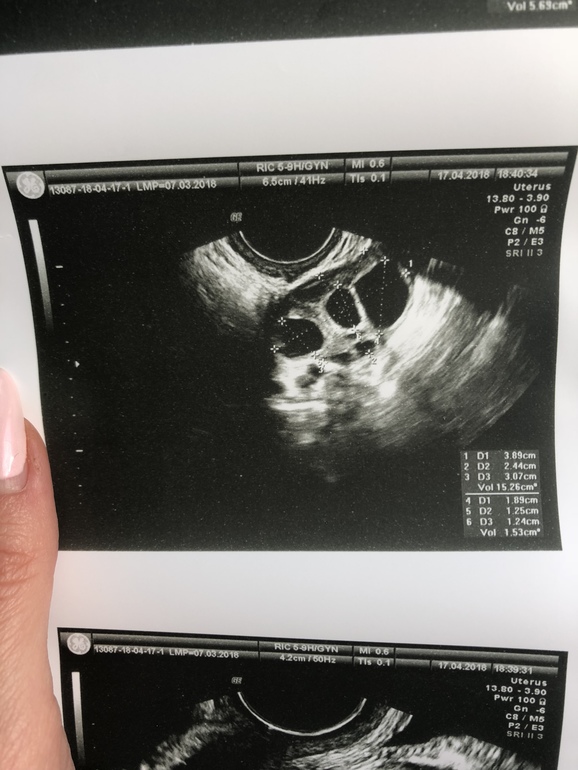

Три фолликула в ЛЯ

Овуляция( тесты на овуляцию)Девочки, привет! Подскажите, пожалуйста, по УЗИ в левом яичнике фолликулы 12.4, 12.5 и 18.9 мм. Те, что 12.4 и 12.5 тоже считаются большими? И перспективными? Они аналогично, должны совулировать? Никогда такого не было, обычно один доминантный, другие меньше 10. Не стимулируюсь ничем)

Если укол ХГЧ ставить не будете, то скорее всего совулирует только ДФ. Если укол будет, то скорее всего и эти дорастут и могут совулировать. У меня на овитреле фоллик 11мм совулировал.